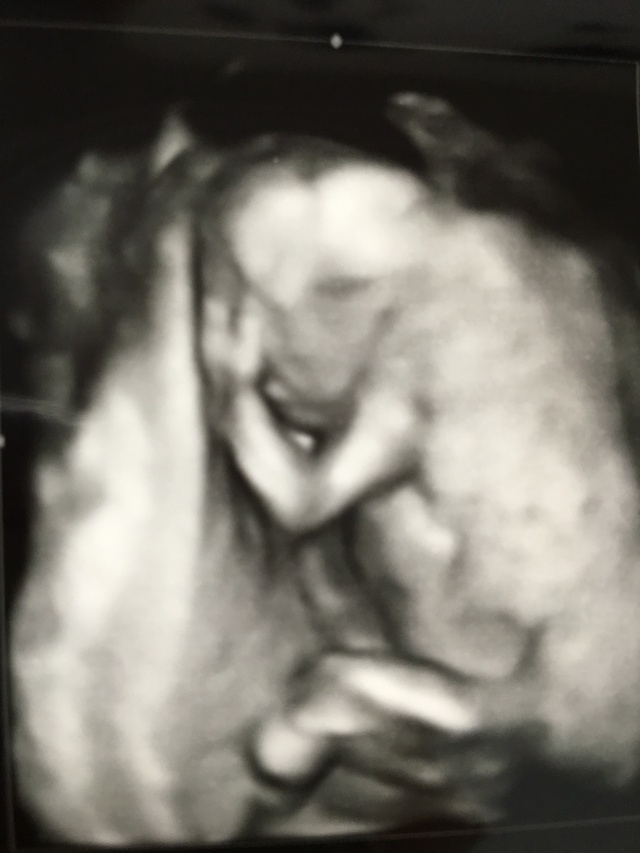

14週5日(14w5d・男の子)|nako08 さん(27歳)

エコー写真撮影時のエピソード:

悪阻は全体的に軽かったが、頭痛がずっとしていた。この日は午後から体調が悪くなり何を食べても吐いてしまい、ずっと寝ていた。

この3D?4D?写真が赤ちゃんをちゃんと写せた最初で最後の写真。その後からはずっと顔の前に手があったり、隙間が無くて3D?4D?写真を撮ってもらえなかった。

だからちゃんと全身が見えて、はっきり写ってるこの写真は宝物。